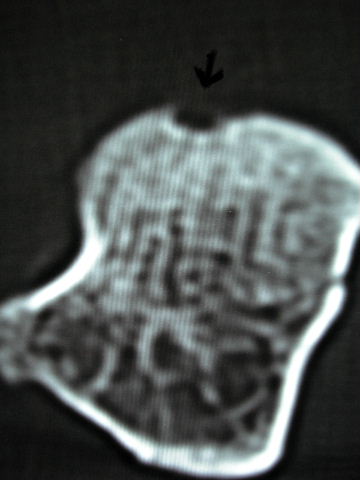

TC exostosis occipital congénica.

TC exostosis occipital congénita.